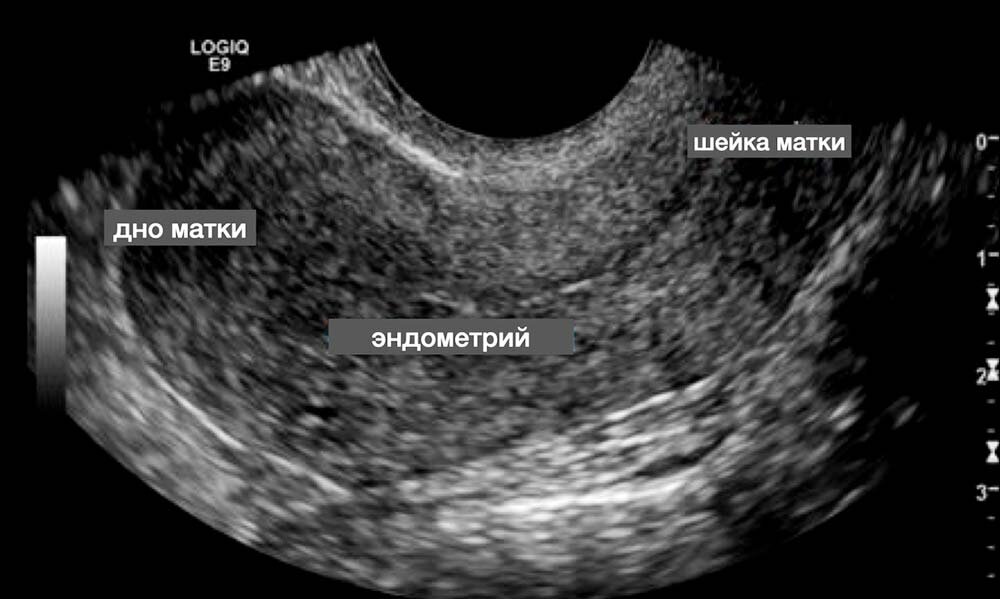

УЗИ снимок матки

- Обязательно УЗИ органов малого таза, если ранее это не проводилось с целью исключения пороков развития.